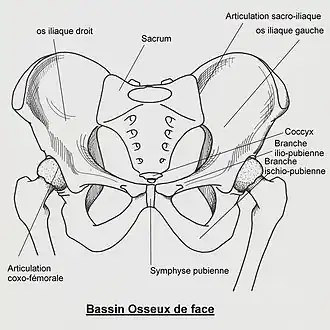

Le sacrum, chez les vertébrés terrestres, est un os du bassin, impair, médian et symétrique, formé de la soudure des vertèbres sacrées ou sacrales.

Le sacrum est situé en dessous de la cinquième vertèbre lombaire et entre les deux os coxaux. Il résulte de la fusion des cinq vertèbres sacrées.

Dans sa moitié supérieure au niveau des deux premières vertèbres sacrées, la surface auriculaire de l'os sacrum forme la surface articulaire qui reçoit la surface auriculaire de l'ilion, zone articulaire de l'os coxal pour former l'articulation sacro-iliaque. En arrière et dans la concavité de la surface articulaire se présente une surface rugueuse la tubérosité de l'os sacrum sur laquelle s'attache le ligament sacro-iliaque postérieur.

À l'avant et au milieu, au niveau de la face supérieure du corps de la première vertèbre sacrée une surface articulaire plane et ovalaire s'articule avec la face inférieure du corps de la cinquième vertèbre lombaire par l'intermédiaire d'un disque intervertèbral. A ce niveau, le sacrum forme avec la colonne lombaire un angle obtus à sommet antérieur : le promontoire.

Le sommet du sacrum présente une surface ovalaire à grand diamètre transversal qui s'articule avec la base du coccyx.